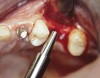

A 53-year-old female was referred for evaluation of a fracture of tooth No. 24. The tooth had been treated endodontically 5 years prior. The radiograph revealed a complete fracture of the tooth involving the crown (Figure 12). Tooth extraction and immediate placement of a an implant that was 10 mm in length and 3.75 in diameter was planned.

At the time of surgery, the tooth was extracted without harvesting any mucosal flap because the implant site was prepared by means of a pilot drill bur (Figure 13) and alternating osteotomes (Figure 14A and Figure 14B). The implant was positioned and showed primary stability. The implant was loaded 2 days after surgery. Then, splinted PFM crowns supported by custom gold abutments were delivered. At 6 months posttreatment, the radiograph revealed no bone resorption and the clinical result was optimal (Figure 15A and Figure 15B).

Figure 14A and Figure 14B Alternating osteotomes were used to prepare the implant site.

Figure 14a  Alternating osteotomes were used to prepare the implant site.

Figure 14a

Figure 14b  Alternating osteotomes were used to prepare the implant site.

Figure 14b